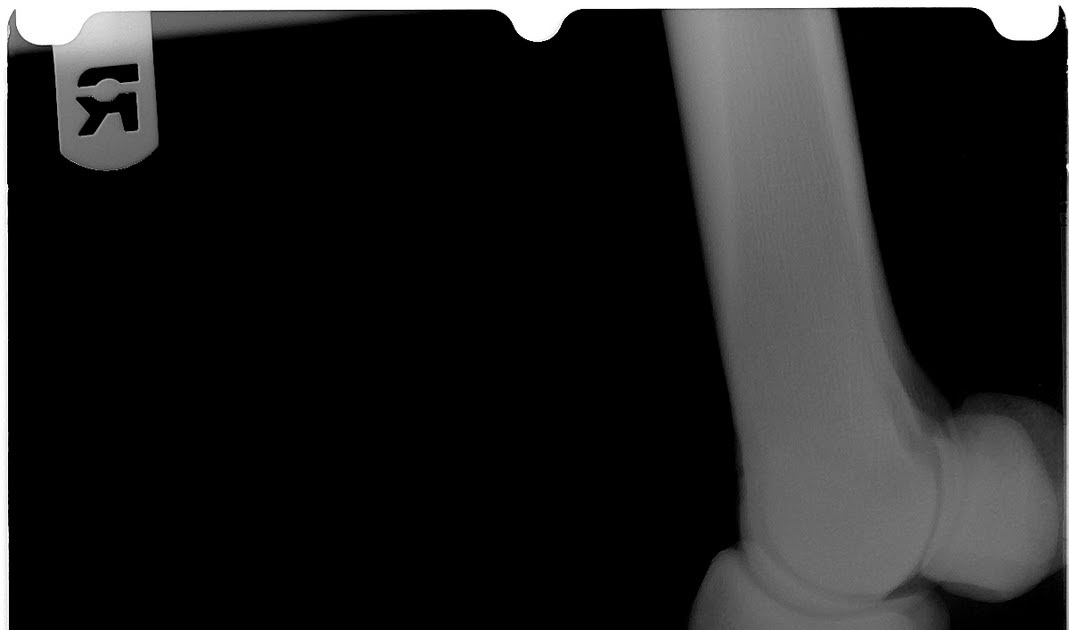

DMPLO front foot radiographs from reticulated giraffe demonstrating Pedal Osteitis Define Pedal osteitis—inflammation of the distal (third) phalanx—is a potential cause of lameness originating from the equine hoof. It is a reaction of the bone in response to a primary insult, such as that caused by horses with a. Pedal osteitis is inflammation of the pedal bone. Affected horses can experience pain and lameness, which may be worse after exercise or. Pedal Osteitis Define.